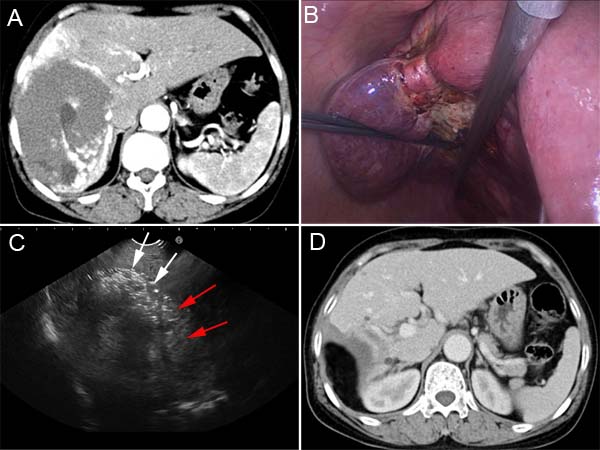

A 60-year-old female was admitted to our hospital because of the enlarging subcapsular hepatic hemangioma on regular imaging follow-up within 3 years. No tumor mass was palpable by physical examination. Contrast-enhanced CT showed a typical hepatic hemangioma in the right lobe (13.1 cm×9.3 cm) (Figure 2A). Laboratory test prior to the tumor resection didn’t find any abnormal values regarding the liver, renal and coagulator function or tumor markers.

The resection margin was marked by diathermy on the surface of hemangioma 1.0 cm away from the border between the normal liver parenchyma and the tumor. RF-induced coagulation was performed along the resection margin by placing the Cool-tip ACTC2025 electrodes into the tumor, which was precisely guided by real-time ultrasound imaging. The substantial coagulation was achieved while the hemangioma tissue along the ablation margin shrank significantly following the RF ablation (Figure 2B). The hepatic hemangioma was dissected along the coagulative necrosis using harmonic scalpel. During the tumor dissection, RF ablation should be repeatedly applied to the tumor if further coagulation is needed. Intraoperative ultrasound imaging was used to determine the boundary of hepatic hemangioma in liver parenchyma, and the ablated lesion became hyperechoic because of outgassing from heated tissues (Figure 2C). The majority of the hemangioma was removed with a 1.0-cm width of coagulated hemangioma left in place. For this patient the coagulation time was 95 min and the dissection time was 50 min. The total number of punctures was 13. Blood loss during resection was 300 ml. In the course of recovery post the procedure, the patient experienced hyperbilirubinemia (42.4 μmol/L of total bilirubin), elevated serum transaminase (801.5 U/L AST and 302.2 U/L ALT) and serum creatinine (190.8 ɥmol/L). All these abnormalities seen in laboratory test resolved after conservative treatment. No blood transfusion and dialysis were needed during perioperative period. A pathological examination confirmed the hepatic cavernous hemangioma. The patient was discharged 12 days after surgery. Three months post the surgery, contrast-enhanced CT confirmed that the hemangioma was completely dissected without any residual tissue (Figure 2D). No appearances of late complications have been observed for 9 months since surgery.

Figure 2: CT and intraoperative photos of case 2. A. Contrast-enhanced CT demonstrated a 13.1 cm hepatic hemangioma in the right lobe. B. Radiofrequency ablation induced the significant shrinking of the hemangioma along the resection margin. C. Intraoperative ultrasound imaging was used to determine the boundary (red arrows) of hepatic hemangioma (white arrows) in liver parenchyma. D. Contrast-enhanced CT shows that the hemangioma was completely resected without residual tissue.